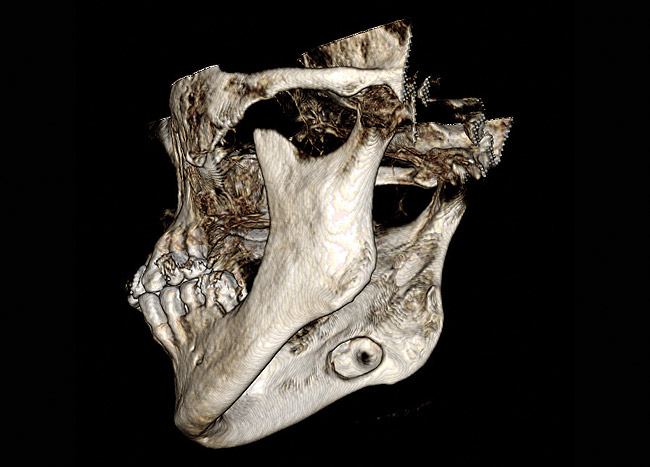

Cone-beam computed tomography, digital volume tomography, and cone beam imaging,2,12 were actually initiated in the area of dentomaxillofacial (mouth, jaw, and neck) imaging as early as 1998.9 In dental maxillofacial imaging, there are four primary areas for its use: pre-surgical visualization on third molars, temporal mandibular joint dysfunction, jaw disease, and dental implant planning (Figure 5). CBCT, which was specifically developed for the maxillofacial region, produces better images than the conventional computed tomography at a considerably lower radiation dose and cost.6 In the past, imaging of these areas of dental and maxillofacial diseases had been performed using plain film and panoramic imaging, but CBCT can enhance a radiographic diagnosis (Figure 6).

Figure 5  Dentomaxillofacial imaging.

Figure 5